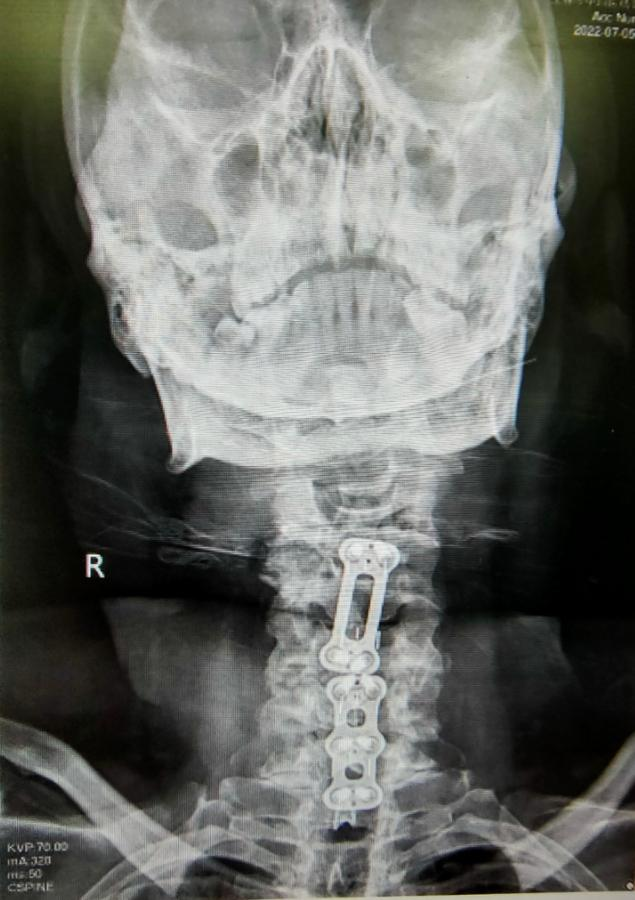

图二:手术后脊椎CT